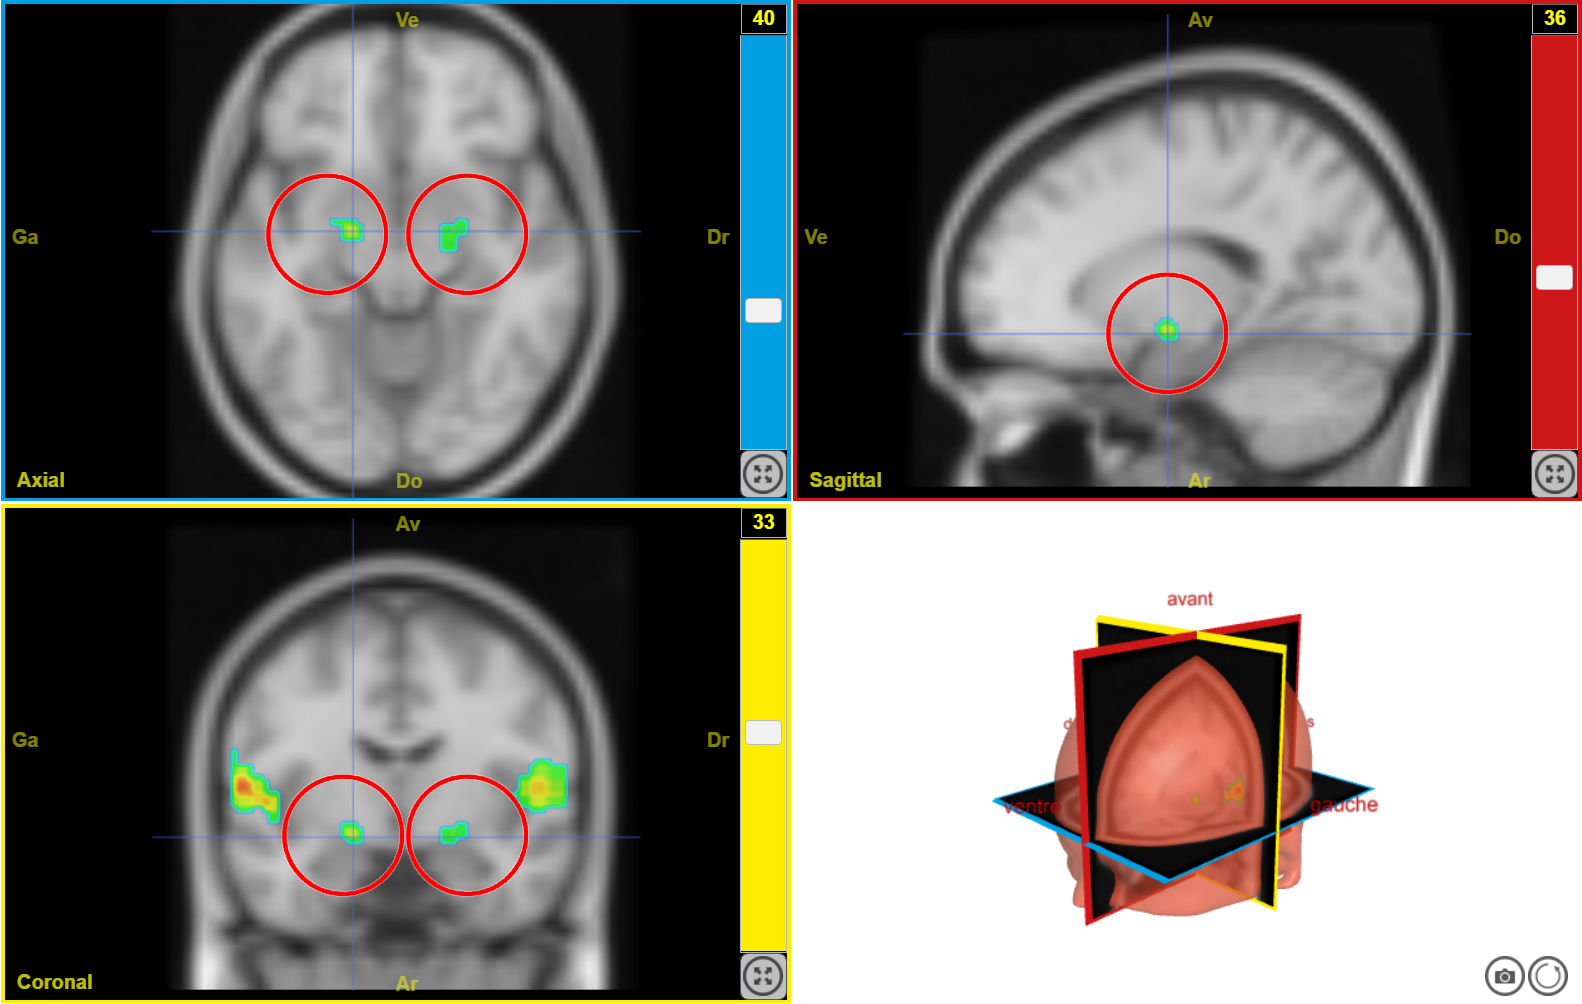

IRMf musique joyeuse 3